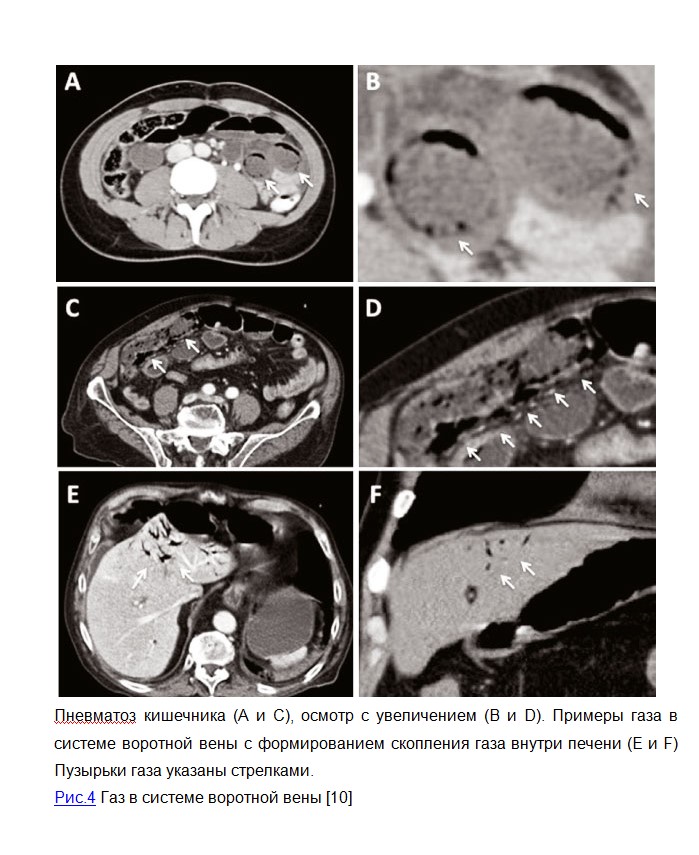

Диагностика. В целом, диагноз кистозного пневматоза кишечника основан на эндоскопии и рентгенологических методах (Рис.1), таких, как обзорная рентгенография и компьютерная томография органов брюшной полости, при этом компьютерная томография имеет большую чувствительность, в том числе для определения такого редкого и грозного проявления кистозного пневматоза, как образования газа в системе воротной вены (Рис. 3 E и F, 4), определение которого на обзорной рентгенограмме связано с высоким уровнем летальности (73-83%). Рентгенологические признаки газа в стенке кишечника могут быть разделены на кистозные и линейный. При кистозном пневматозе на фоне вздутия кишки определяются ячеистые структуры в виде виноградных скоплений или сотовидных теней вдоль стенки кишечника, обусловленные тесно расположенными кистозными образованиями разного размера и конфигурации (Рис. 1 А,D). [1,3] Линейный пневматоз характеризуется наличием полос, расположенных параллельно стенке кишки, циркулярным складкам или гаустрам. (Рис.2). Чаще линейный пневматоз связан с ишемией кишечника или инфарктом. Так же рентгенологические методы обследования позволяют выявить наличие свободного газа в брюшной полости. [5,8,10]

Особенности визуализации кистозного пневматоза кишечника. A: на ирригоскопии выявлены множественные полиповидные поражения с тенями воздуха (указаны стрелкой) и виноградоподобным интрамуральным газом на всем протяжении; B: Колоноскопия: множественные круглые полиповидные суэпителиальные образования с ровной поверхностью (указаны стрелкой); C: Эндоскопическое УЗИ: гиперэхогенные образования с акустической тенью в подслизистом слое (указаны стрелкой); D: Обзорная рентгенография левого верхнего квадранта брюшной полости, показывающая дилатацию кишечника и мелкие линейные, круглые серебристые области (стрелка) в стенке толстой кишки.